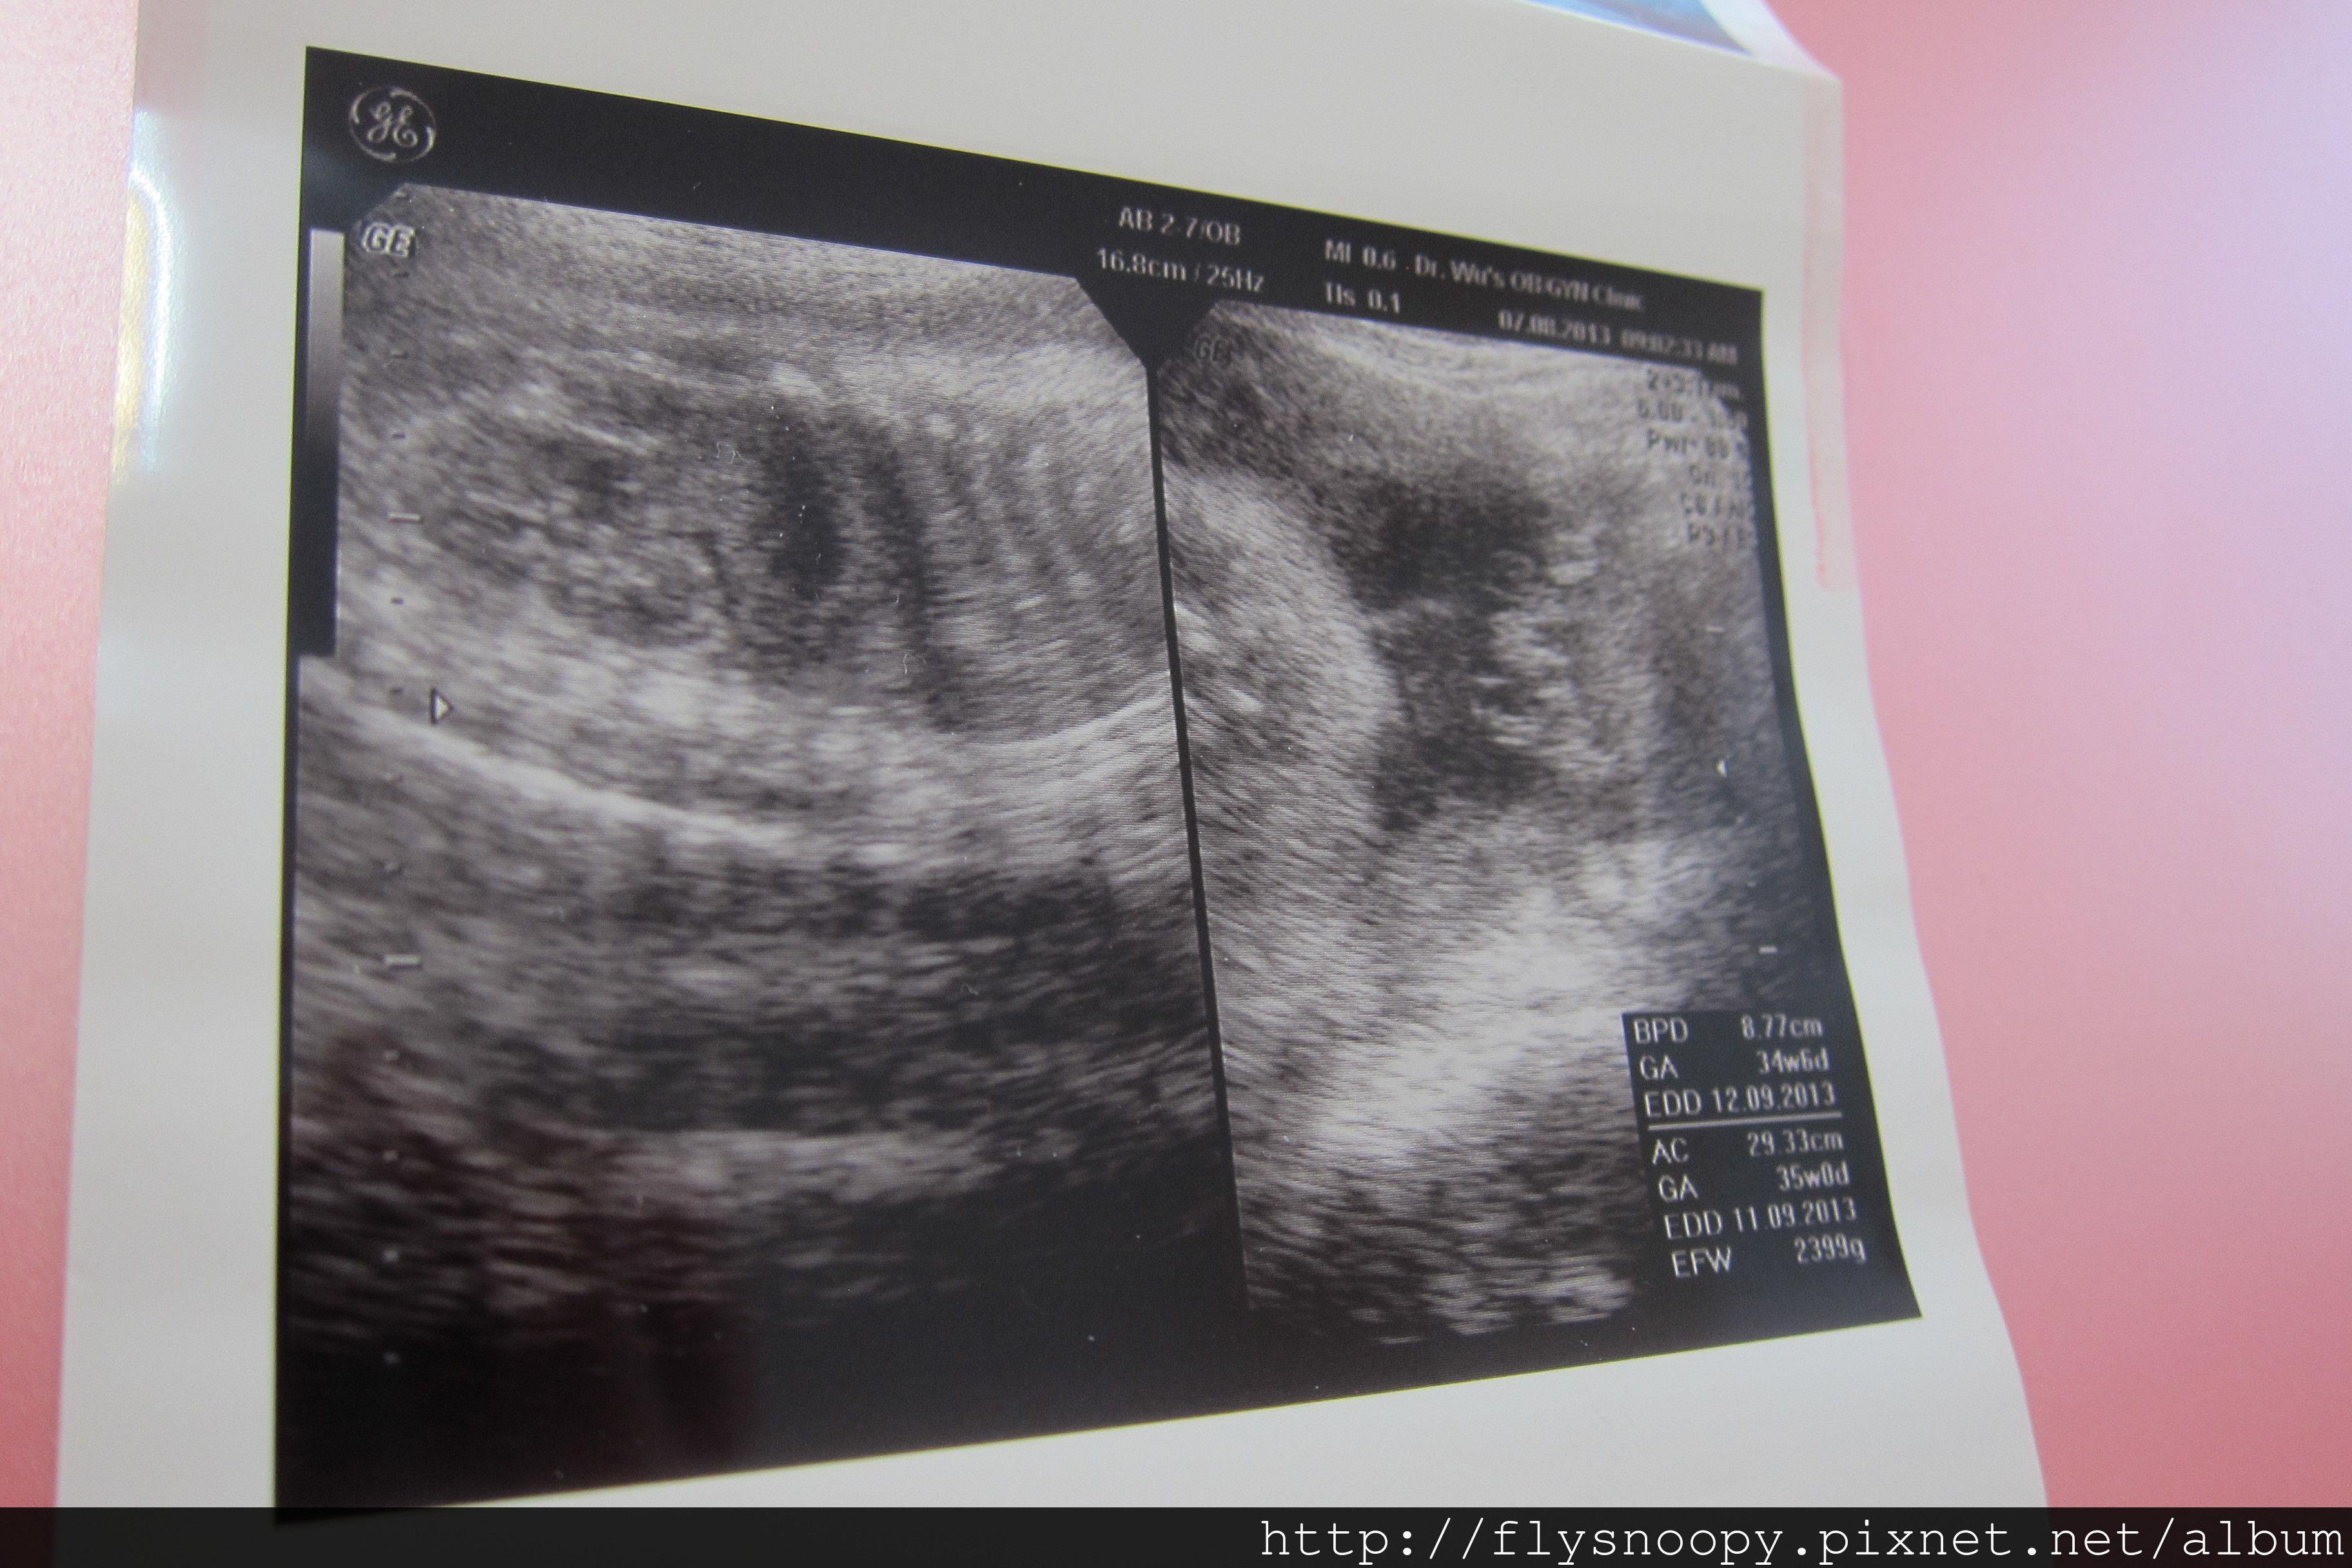

8/7第9次產檢

第九次產檢記錄

EFW:2399